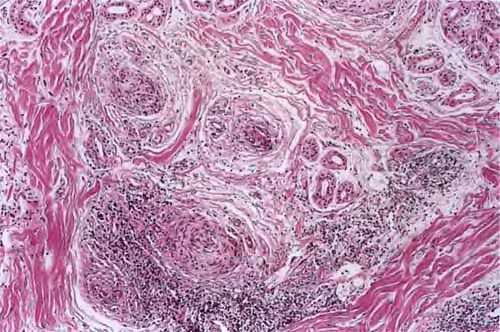

Read MoreAngiokeratoma = القرنوم الوعائي Angiokeratoma Corporis DiffusumFabry Histology shows numerous, dilated, thin-walled, endothelial-lined, blood-engorged capillaries in the papillary dermis, with an overlying hyperkeratotic epidermis. Careful inspection may reveal cytoplasmic vacuoles containing lipid in the endothelial cells, fibroblasts, and pericytes. However, in most patients, histologic findings essentially are identical to those of other […]